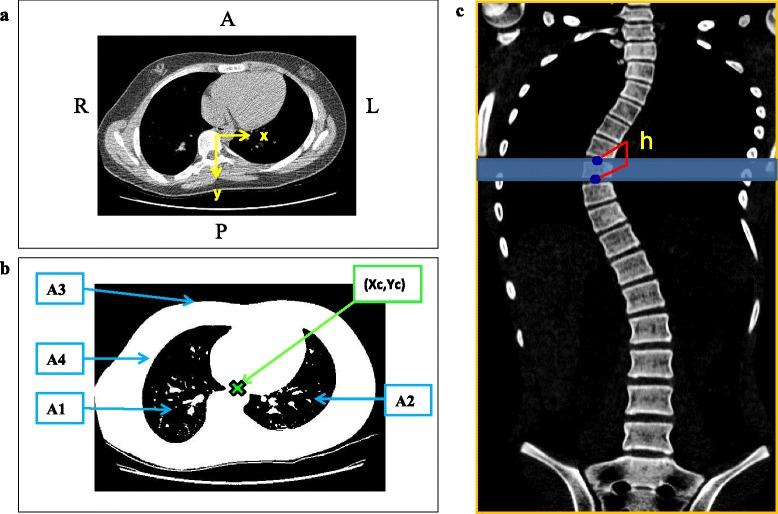

METHODS

Existing low-dose CT scans were used to estimate torso segment masses and joint moments for 20 female scoliosis patients. Intervertebral joint moments at each vertebral level were found by summing the moments of each of the torso segment masses above the required joint.